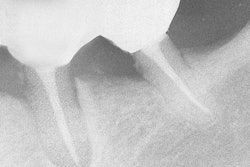

Vertical root fracture is a common and serious complication of root canal therapy that can result in treatment failure and tooth extraction. Therefore, clinicians are eager to prevent these fractures and strengthen endodontically treated roots, such as by using gutta-percha or Resilon to obturate canals.

The final review analysis included more than 650 roots. Unsurprisingly, virgin teeth were significantly stronger than teeth obturated with either material. However, teeth obturated with Resilon were significantly less likely to experience a vertical root fracture than teeth with unfilled root canal treatment, the researchers found.

The same was not true for teeth filled with gutta-percha/AH plus, which performed significantly worse than teeth with unfilled root canals and roots obturated with Resilon.

"Compared with gutta-percha, Resilon shows superior bonding potential when applied in combination with a resin-based sealer," the review authors wrote. "Therefore, the Resilon system has a superior ability to reinforce instrumented roots than does the gutta-percha/AH plus obturation system."